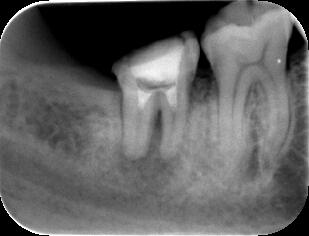

(2)初見では抜歯もしくは遠心根を抜去(ヘミセクション)を考慮しましたが、20代前半で

まだ若いため、約1年半をかけて根の治療を行いました。 ![]() ![]() ![]()

パノラマ画像:黒く写っている病巣が徐々に小さくなっていく様子が分かります。